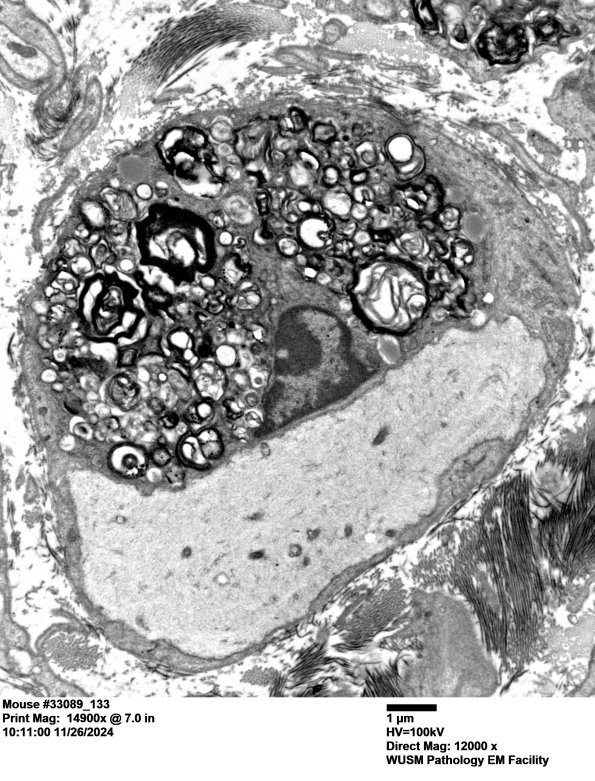

Washington University Experience | PERIPHERAL NEUROPATHY | 6 AXONAL DEMYELINATION (BASIC PROCESS) | 2A3 Mouse #33089 (Case 2) 133AA.jpg

A demyelinated axon with adjacent Schwann cell debris. (electron micrograph)